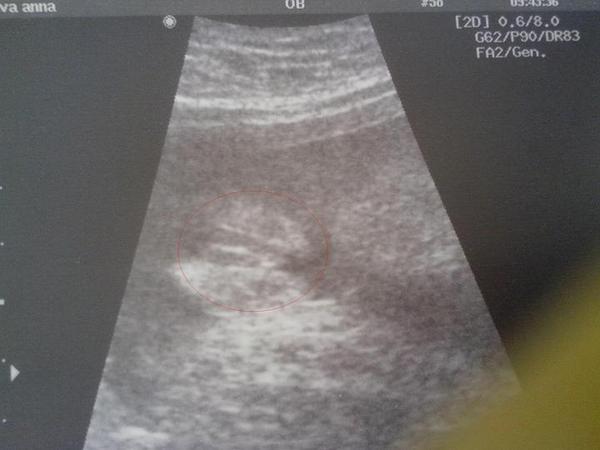

@nik123 PORADÍTE MI?? Holka nebo kluk???

@antymania666 Dobrý den a co tahle fotečka, je to holka???